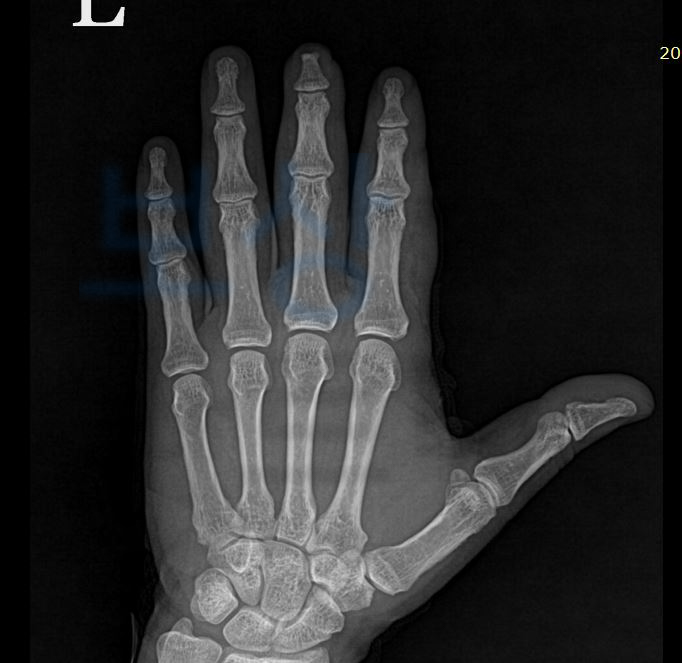

위 재해경위 그대로, 콘베이어에 왼손이 빨려 들어가 큰 사고를 당하셨습니다. 이 사고로 인해 김@@님은

좌측수부 압궤상 손상(탈장갑손상)

좌측 수부 제 2,3수지 신전건 부분 파열

질병분류기호 : S67.8 S66.70 이로 인해 김@@님은 수술적 치료를 받아 4주 진단을 받으셨습니다.